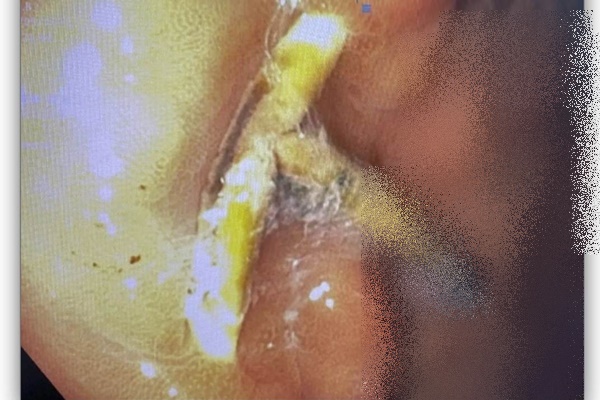

Hình ảnh vòng tránh thai đi lạc sang dạ dày. Ảnh: BV cung cấp

Qua thăm khám, nội soi thực quản, dạ dày, tá tràng và chụp CT scanner, các bác sĩ nhận thấy dị vật dạng dụng cụ tránh thai đâm xuyên thành dạ dày.